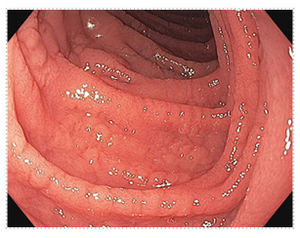

- Can be visually normal, but findings may include scalloping of the small bowel, prominence of blood vessels, nodularity, flattening of the villi, and ulcers

Endoscopic image of small intestinal mucosa with abnormal appearance consistent with celiac disease.